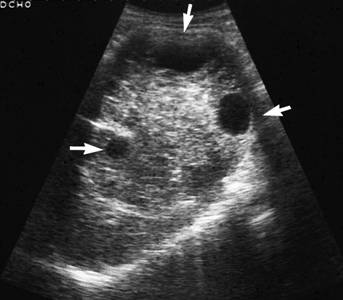

- УЗИ. Ультразвуковая диагностика позволяет выявить любые видимые новообразования в почках. Этот метод обследования является обязательным при подозрении на кисту.